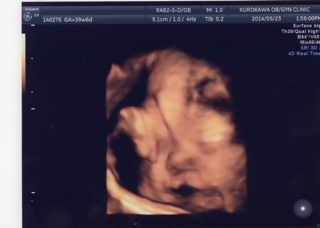

テーマ:妊娠中のできごと 今日は妊婦健診! 15:15(午後10番目)予約でちょっと早めに14:50に受付。 「まだ午前中の診察が終わっていないので、結構待つかもしれません。外出の際は一言ご連絡お願いします。」 と言われましたが、外は大雨だったため 、外出しないでとりあえずは院内で待つことに。 いつものように受付後に自分で採尿&血圧測定。(14:50〜15:00) 15:10に助産師さんに呼ばれ、体重と浮腫みチェック。 体重は先週から+0.2kg(トータル+7.5kg ) 15:15〜15:40 NST(ノンストレステ...